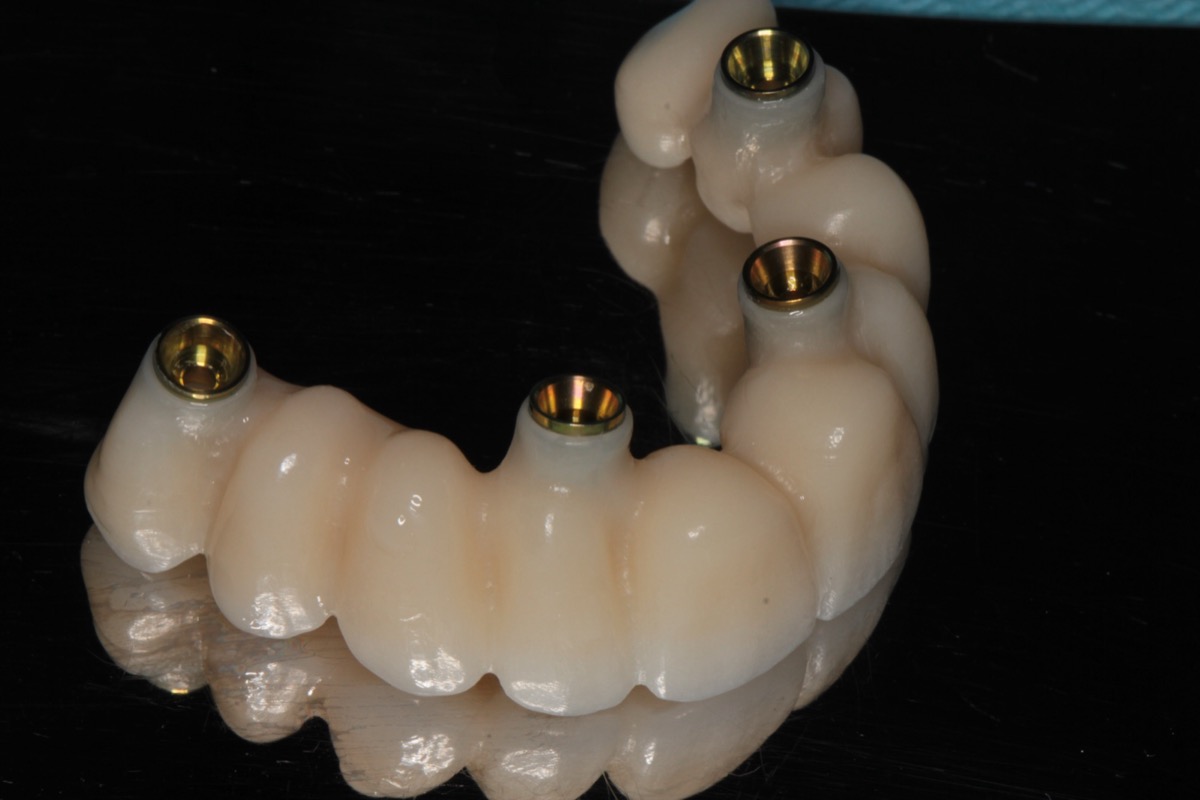

Po dobraniu odpowiednich elementów łączących, pobierany jest cyfrowy skan wewnątrzustny, a następnie laboratorium protetyczne przystępuje do tworzenia pracy tymczasowej z wysokiej jakości materiałów takich jak biokompatybilne, przyjazne tkankom i pacjentowi tworzywa.

W tymczasowej wersji uśmiechu pacjent funkcjonuje najczęściej około 3 miesiące. Gdy tytanowe implanty zrosną się z kością (osteointegracja), jama ustna jest gotowa do osadzenia pracy ostatecznej.

Całkowity koszt obejmuje zabieg chirurgiczny, czyli wszczepienie czterech implantów (cena pojedynczego implantu dla all-on-4 mieści się w zazwyczaj w przedziale 3 500 – 3 850 zł), a także – jeśli jest to konieczne – zabiegi regeneracyjne, przeszczep kości oraz ekstrakcje zębów. W wycenie uwzględnia się również koszt pracy protetycznej tymczasowej – nowoczesne technologie najczęściej pozwalają na osadzenie przykręcanych mostów dentystycznych już bezpośrednio po zabiegu - bez konieczności stosowania protez.

Po około 3 miesiącach gojenia oraz kontrolnym badaniu RTG (np. tomografii komputerowej CBCT) wykonuje się pracę ostateczną, obejmującą 10 lub 12 koron na implantach. Koszt finalnej rekonstrukcji wynosi od 33 000 zł – cena zależy od zastosowanych materiałów, komponentów protetycznych oraz ilości koron w łuku zębowym.